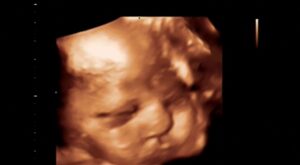

Sera positiva ayudaaa

Non classé

hay 9 años